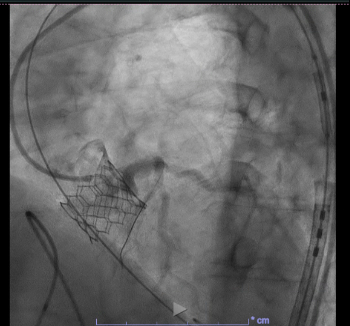

Case: A 62-year-old woman with severe aortic stenosis and multiple comorbidities—including prior stroke, COPD, and peripheral vascular disease—was referred for transfemoral TAVR. Preprocedural CT angiography demonstrated a systolic LM coronary height of 8.36 mm, placing her at high risk for ACO. A 23 mm Edwards SAPIEN 3 Resilia valve was successfully deployed under rapid ventricular pacing. Prophylactic left main protection was achieved by positioning a coronary guidewire via a 6 French guiding catheter from left femoral arterial access. After deployment, this coronary guidewire was jailed at the upper end of the sapient valve. Post-deployment angiography raised suspicion for left main compromise by the displaced left coronary cusp, visualized as a hazy filling defect.

Balloon angioplasty was performed using a 3.0 x 12 mm catheter, which resulted in partial improvement of angiographic appearance but did not fully resolve the haziness. IVUS catheter delivery initially failed but succeeded after introducing a second guidewire through the upper frame cell of the transcatheter valve. IVUS imaging revealed a preserved LM luminal area of >20 mm with no evidence of ostial narrowing or leaflet impingement. The jailed guidewire was safely removed without further intervention.

Decision-making: Despite equivocal angiography, IVUS provided definitive confirmation of LM patency and ruled out true obstruction. This guided the clinical decision to defer coronary stenting and pursue a conservative strategy. In contrast to cases requiring chimney stenting or BASILICA, this approach avoided permanent hardware and minimized procedural risk. This case illustrates the critical role of IVUS in clarifying ambiguous findings and enabling individualized management in anatomically high-risk TAVR.